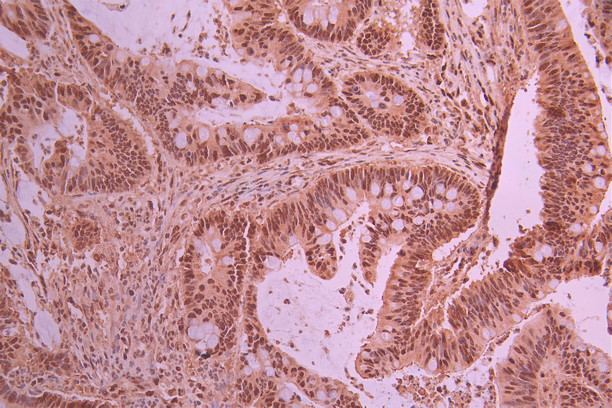

IHC image of CSB-RA074950A0HU diluted at 1:100 and staining in paraffin-embedded human colorectal cancer performed on a Leica BondTM system. After dewaxing and hydration, antigen retrieval was mediated by high pressure in a citrate buffer (pH 6.0). Section was blocked with 10% normal goat serum 30min at RT. Then primary antibody (1% BSA) was incubated at 4°C overnight. The primary is detected by a Goat anti-rabbit polymer IgG labeled by HRP and visualized using 0.05% DAB.